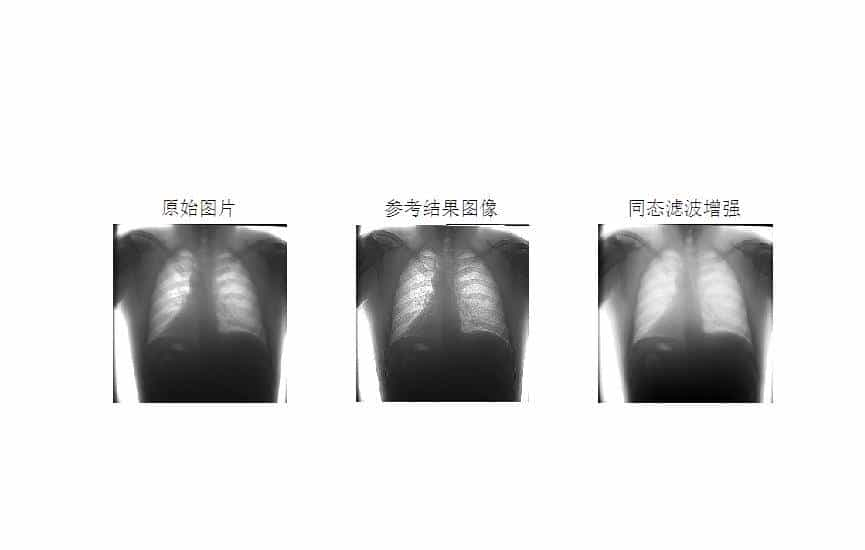

MATLAB环境下使用同态滤波方法进行医学图像增强

同态滤波是一种结合了频率过滤和灰度变换的方法,它以图像的照度反射模型作为频域的处理基础,分别对低频信息进行增强,高频信息进行抑制,可以有效解决图像上照度不均匀和 动态范围过大对图像产生影响的问题,在不损失亮区细节信息的同时,有效增强暗区的细节信息。

本文以医学图像为例,使用同态滤波方法进行医学图像增强。

结果如下: